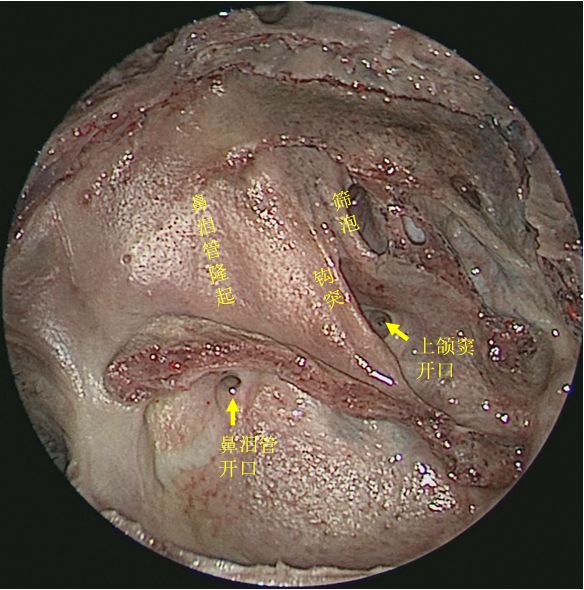

切除右侧中鼻甲后观察右鼻腔侧壁

切除中、下鼻甲后抵近观察右侧鼻腔侧壁